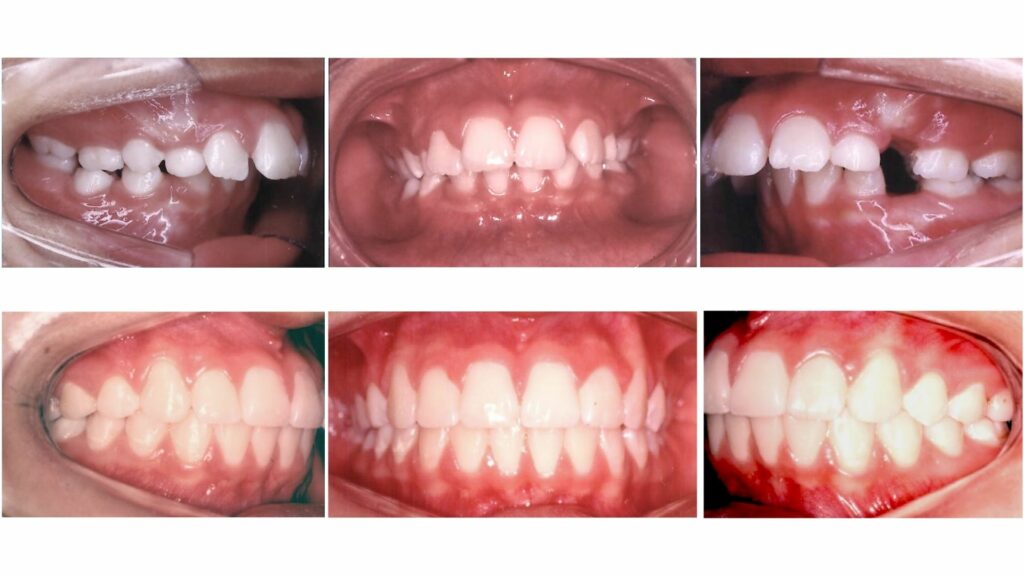

A Ortodontia tem como objetivo corrigir a posição dos ossos maxilares e dos dentes que estão mal posicionados, condição conhecida como má oclusão.

A má oclusão pode afetar os dentes em diferentes direções (vertical, horizontal e transversal). Por isso, o tratamento deve ser feito de forma específica (a arcada é tratada por setores), levando em conta cada caso individualmente. A Ortodontia Bioprogressiva adota esse conceito, tratando os dentes e os segmentos de forma personalizada.

A Ortodontia Bioprogressiva corrige o que está errado sem prejudicar o que já está bom. O diagnóstico vai além do uso de aparelhos. A Bioprogressiva foca nas necessidades específicas de cada paciente, oferecendo um diagnóstico individualizado para um tratamento mais eficaz.